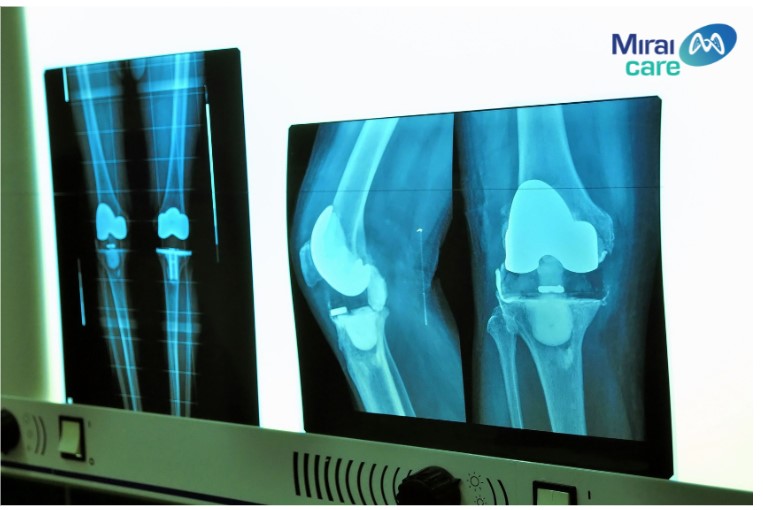

Điều trị viêm khớp gối bằng liệu pháp tế bào gốc theo cơ chế sử dụng tế bào gốc tự thân được các chuyên gia đánh giá cao.  Tế bào gốc sẽ được tiêm vào vùng khớp bị tổn thương giúp tái tạo cấu trúc khớp, có tác dụng giảm viêm trong khớp, ngoài ra còn có tác dụng trong việc khôi phục xương sụn và giảm đau mạnh. So với các phương pháp khác, liệu pháp tế bào gốc chữa bệnh viêm khớp gối có ưu điểm là không mất thời gian hồi phục và không xâm lấn.

miraicare-3.jpg

Hiệu quả rõ rệt của phương pháp điều trị viêm khớp gối bằng tế bào gốc